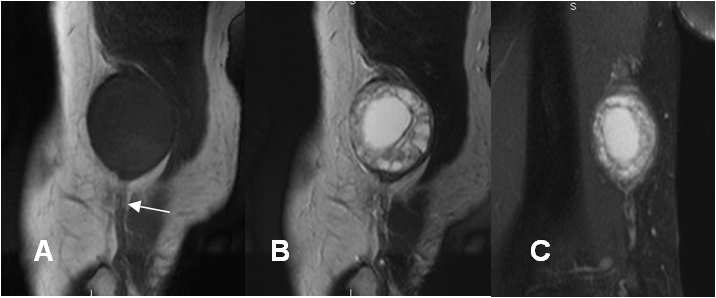

Fig 180. Neurofibroma.

A: RM sagital en T1. Lesión fusiforme central e isointensa al músculo, que presenta continuidad con el nervio ulnar.

B: RM sagital en T2 y C: RM coronal en STIR. Imagen heterogénea, con componente quístico central e hiperintenso en ambas secuencias.